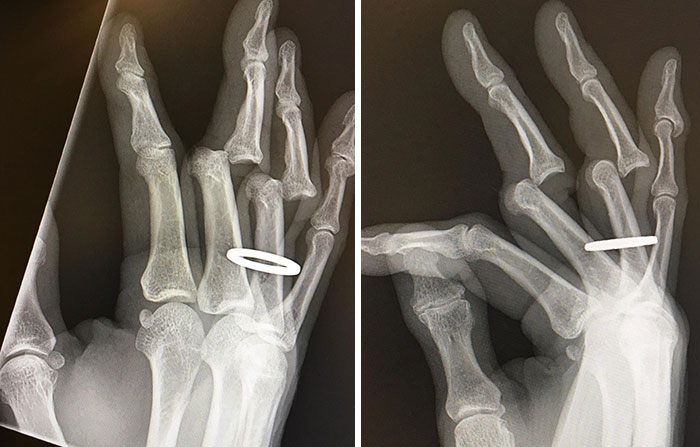

Just Received My X-Rays From Saturday’s Debacle. They Had To Cut My Ring Off Before Returning My Bones To Their Full Upright And Locked Position

My fingers are still sore/stiff/swollen but mostly functional